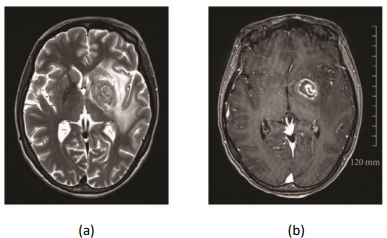

Mulher de 31 anos é internada em um hospital psiquiátrico com quadro de desorientação. Medicada com neurolépticos, evolui, durante a internação, com cefaleia, hemiparesia à direita e um episódio de crise convulsiva tônico-clônica generalizada. Exame clínico minucioso revela anemia, prurigo estrófulo, onicomicose em múltiplos pododátilos e candidose oral. É então submetida à ressonância nuclear magnética, que revela, nas sequências ponderadas em T2 e em T1, após administração de meio de contraste:

(a) Sequência em T2 demonstrando sinal de alvo “concêntrico” com alternância de aros concêntricos hiperintensos e hipointensos; (b) Sequência pós-contraste em T1 demonstrando sinal de alvo “excêntrico” com aro periférico de captação de contraste e nódulo focal lateral esquerdo com realce excêntrico.